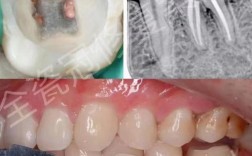

- 全瓷牙冠: 这是最理想的选择,全瓷材料(如氧化锆、锂硅酸盐玻璃陶瓷等)是非磁性的,在MRI中几乎不产生伪影,对图像质量和安全性没有任何影响。

- 全瓷牙冠: 最佳选择,对MRI无影响,安全。